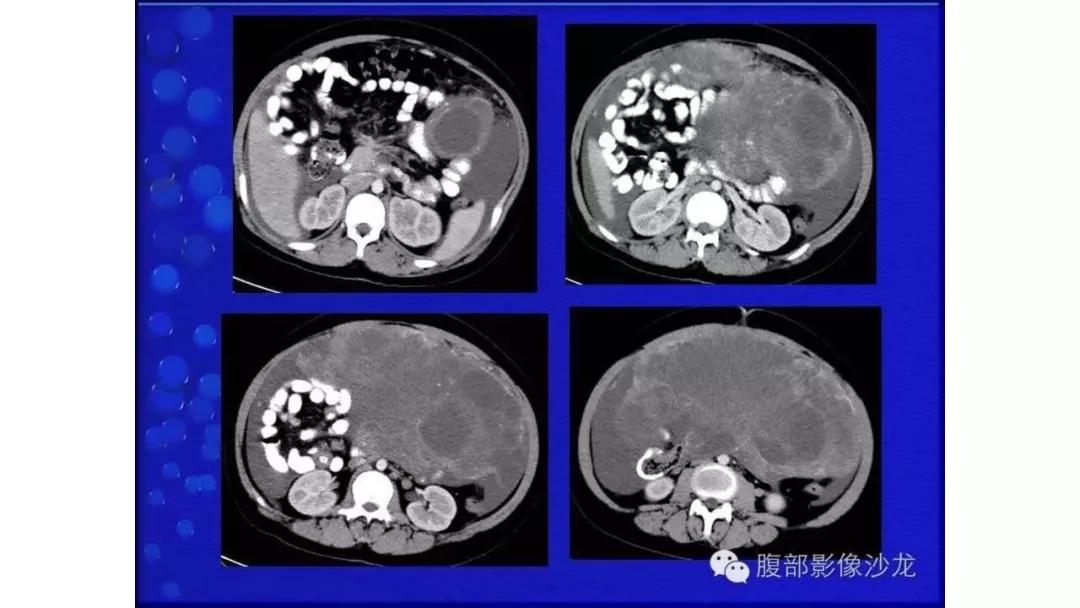

病理:浆液性囊腺癌

病理:颗粒细胞瘤